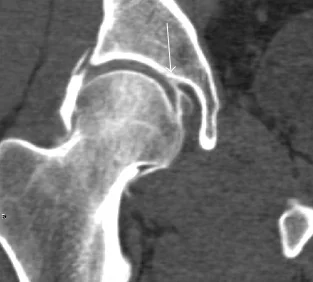

CT: Fortunately for emergency physicians, CT scan of the hip without IV contrast is also appropriate for further evaluation of negative hip x-rays.iii The reason that the ACR lists CT second is due to the balancing of risks and benefits associated with the increased radiation of CT scan versus MRI.[3] However, from an emergency department perspective, CT is typically much easier and quicker to obtain and can increase efficiency and patient throughput. (Figure 4)